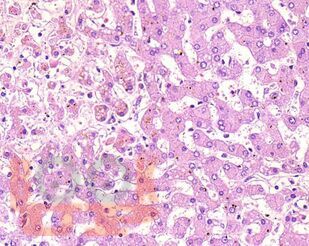

В учебном пособии представлен теоретический материал, перечень макропрепаратов и микропрепаратов, демонстрирующих типовые проявления патологических процессов и нозологических форм заболеваний. В цветных иллюстрациях и в описании микропрепаратов сделан акцент на наиболее важных гистологических изменениях, позволяющих на светооптическом уровне диагностировать и дифференцировать состояния, отклоняющиеся от нормы, в том числе с использованием различных гистологических окрасок. Пособие помогает выделить главные аспекты изучаемых патологических процессов, организовать и конкретизировать учебный процесс.